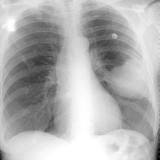

Mets

Album: Mets

Date: 02/18/2006

Size: 52 items

Views: 39903